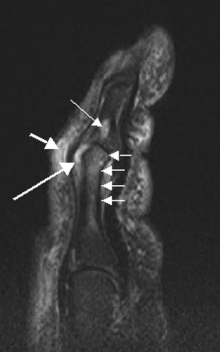

- Дактилит — это острое или хроническое воспаление пальца, клинически проявляющееся болью, цианотическим окрашиванием пальцев, плотным отеком пальцев, болевым ограничением сгибания, характерной для псориатического артрита сосискообразной деформацей пальцев. Является типичным признаком псориатического артрита, возникающий в результате одновременного поражения сгибателей и/или разгибателей пальцев, а также артрита межфаланговых суставов.

- Теносиновит проявляется болью, припуханием по ходу сухожилий, а также ограничением функции (сгибание пальцев).